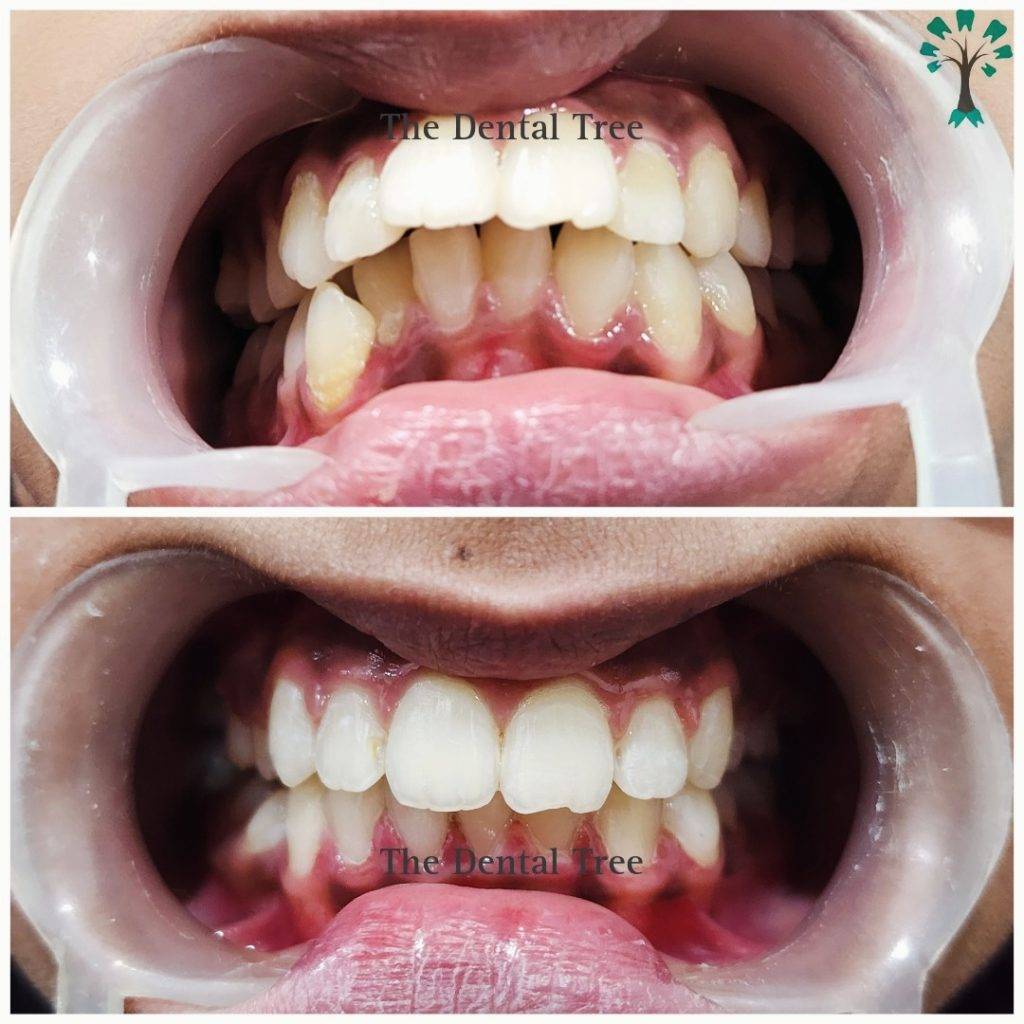

Treatment Gallery

At The Dental Tree & Facial Cosmetic Centre, the centre of our universe is our patients. Satisfaction of our patients has always been our top priority and always will be. This is the reason why we are the Best Dental Clinic in Indirapuram and why we do what we do.

- Dentists also offer cosmetic procedures such as teeth whitening, veneers, and dental implants to improve the appearance of the smile.

Our Gallery